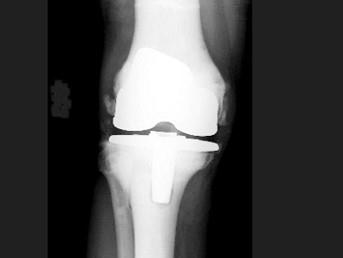

男,21岁,曾多次有过骨折史,结合图像,最可能的诊断是?(?)A.石骨症B.成骨不全C.畸形性骨炎D.转移性骨肿瘤E.氟骨症

问题 男,21岁,曾多次有过骨折史,结合图像,最可能的诊断是?(?)

选项 A.石骨症 B.成骨不全 C.畸形性骨炎 D.转移性骨肿瘤 E.氟骨症

答案 A